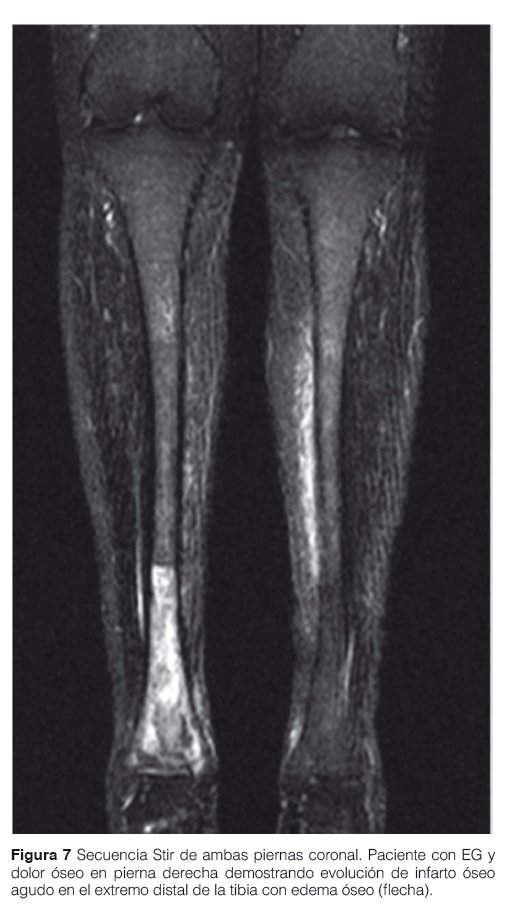

La evaluación de la enfermedad ósea es necesaria tanto al diagnóstico como en el seguimiento del paciente por lo menos una vez al año o frente a sintomatología aguda (dolor óseo-crisis óseo)9,10 (Fig. 7 y 8).